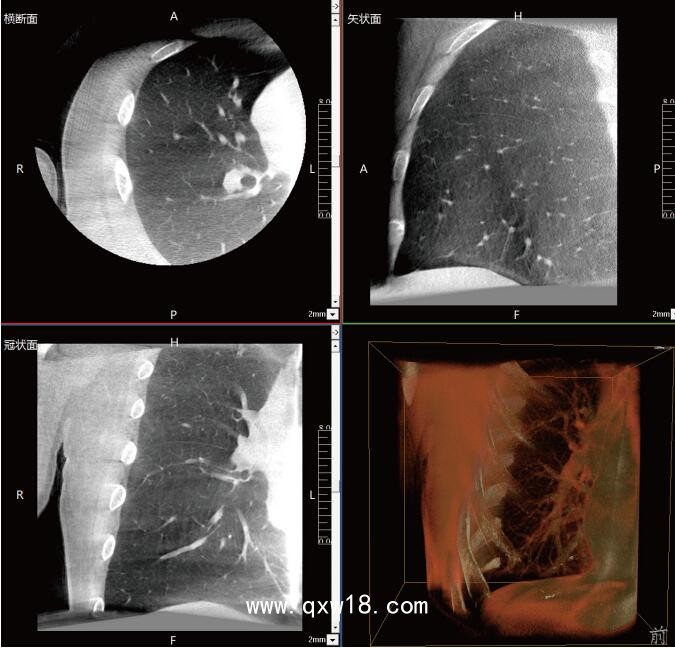

呼吸介入C型臂臨床應(yīng)用-普愛醫(yī)療三維C型臂CT產(chǎn)品說明:

近年來,在肺部手術(shù)領(lǐng)域的應(yīng)用呈現(xiàn)出顯著的增長(zhǎng)態(tài)勢(shì)。這一技術(shù)不僅滿足了臨床指導(dǎo)穿刺、精準(zhǔn)確認(rèn)病變與針尖位置關(guān)系的迫切需求,更通過大量臨床研究的驗(yàn)證,證明了其在肺結(jié)節(jié)診斷、定位及治療中的有效性和安全性。

《中國專家對(duì)CBCT引導(dǎo)下肺結(jié)節(jié)的診斷、定位和治療的共識(shí)》提到C型臂CT系統(tǒng)憑借其強(qiáng)大的功能,能夠充分滿足透視監(jiān)測(cè)、病變與工具位置確認(rèn)、消融區(qū)監(jiān)測(cè)以及并發(fā)癥檢查等多元化的臨床需求。因此,在考慮設(shè)施條件(如導(dǎo)航設(shè)備、手術(shù)室空間)、靶病灶特性(大小、密度)、麻醉方法及干預(yù)路徑(經(jīng)支氣管或經(jīng)胸)等多重因素的基礎(chǔ)上,C型臂CT系統(tǒng)成為了眾多醫(yī)療機(jī)構(gòu)的優(yōu)選方案。

呼吸介入C型臂CT的臨床適應(yīng)癥廣泛,包括支氣管鏡檢查、肺結(jié)節(jié)穿刺活檢、肺結(jié)節(jié)定位、肺結(jié)節(jié)消融以及經(jīng)支氣管肺結(jié)節(jié)診療等多個(gè)領(lǐng)域。其臨床應(yīng)用價(jià)值不言而喻:在經(jīng)支氣管干預(yù)肺結(jié)節(jié)時(shí),透視功能可精準(zhǔn)引導(dǎo)支氣管鏡與活檢鉗直達(dá)靶結(jié)節(jié);重建的三維圖像則能清晰展示干預(yù)工具的位置,確保操作的準(zhǔn)確性。在肺結(jié)節(jié)消融過程中,呼吸介入C型臂CT更是實(shí)現(xiàn)了高精度定位,有效提升了治療效果。